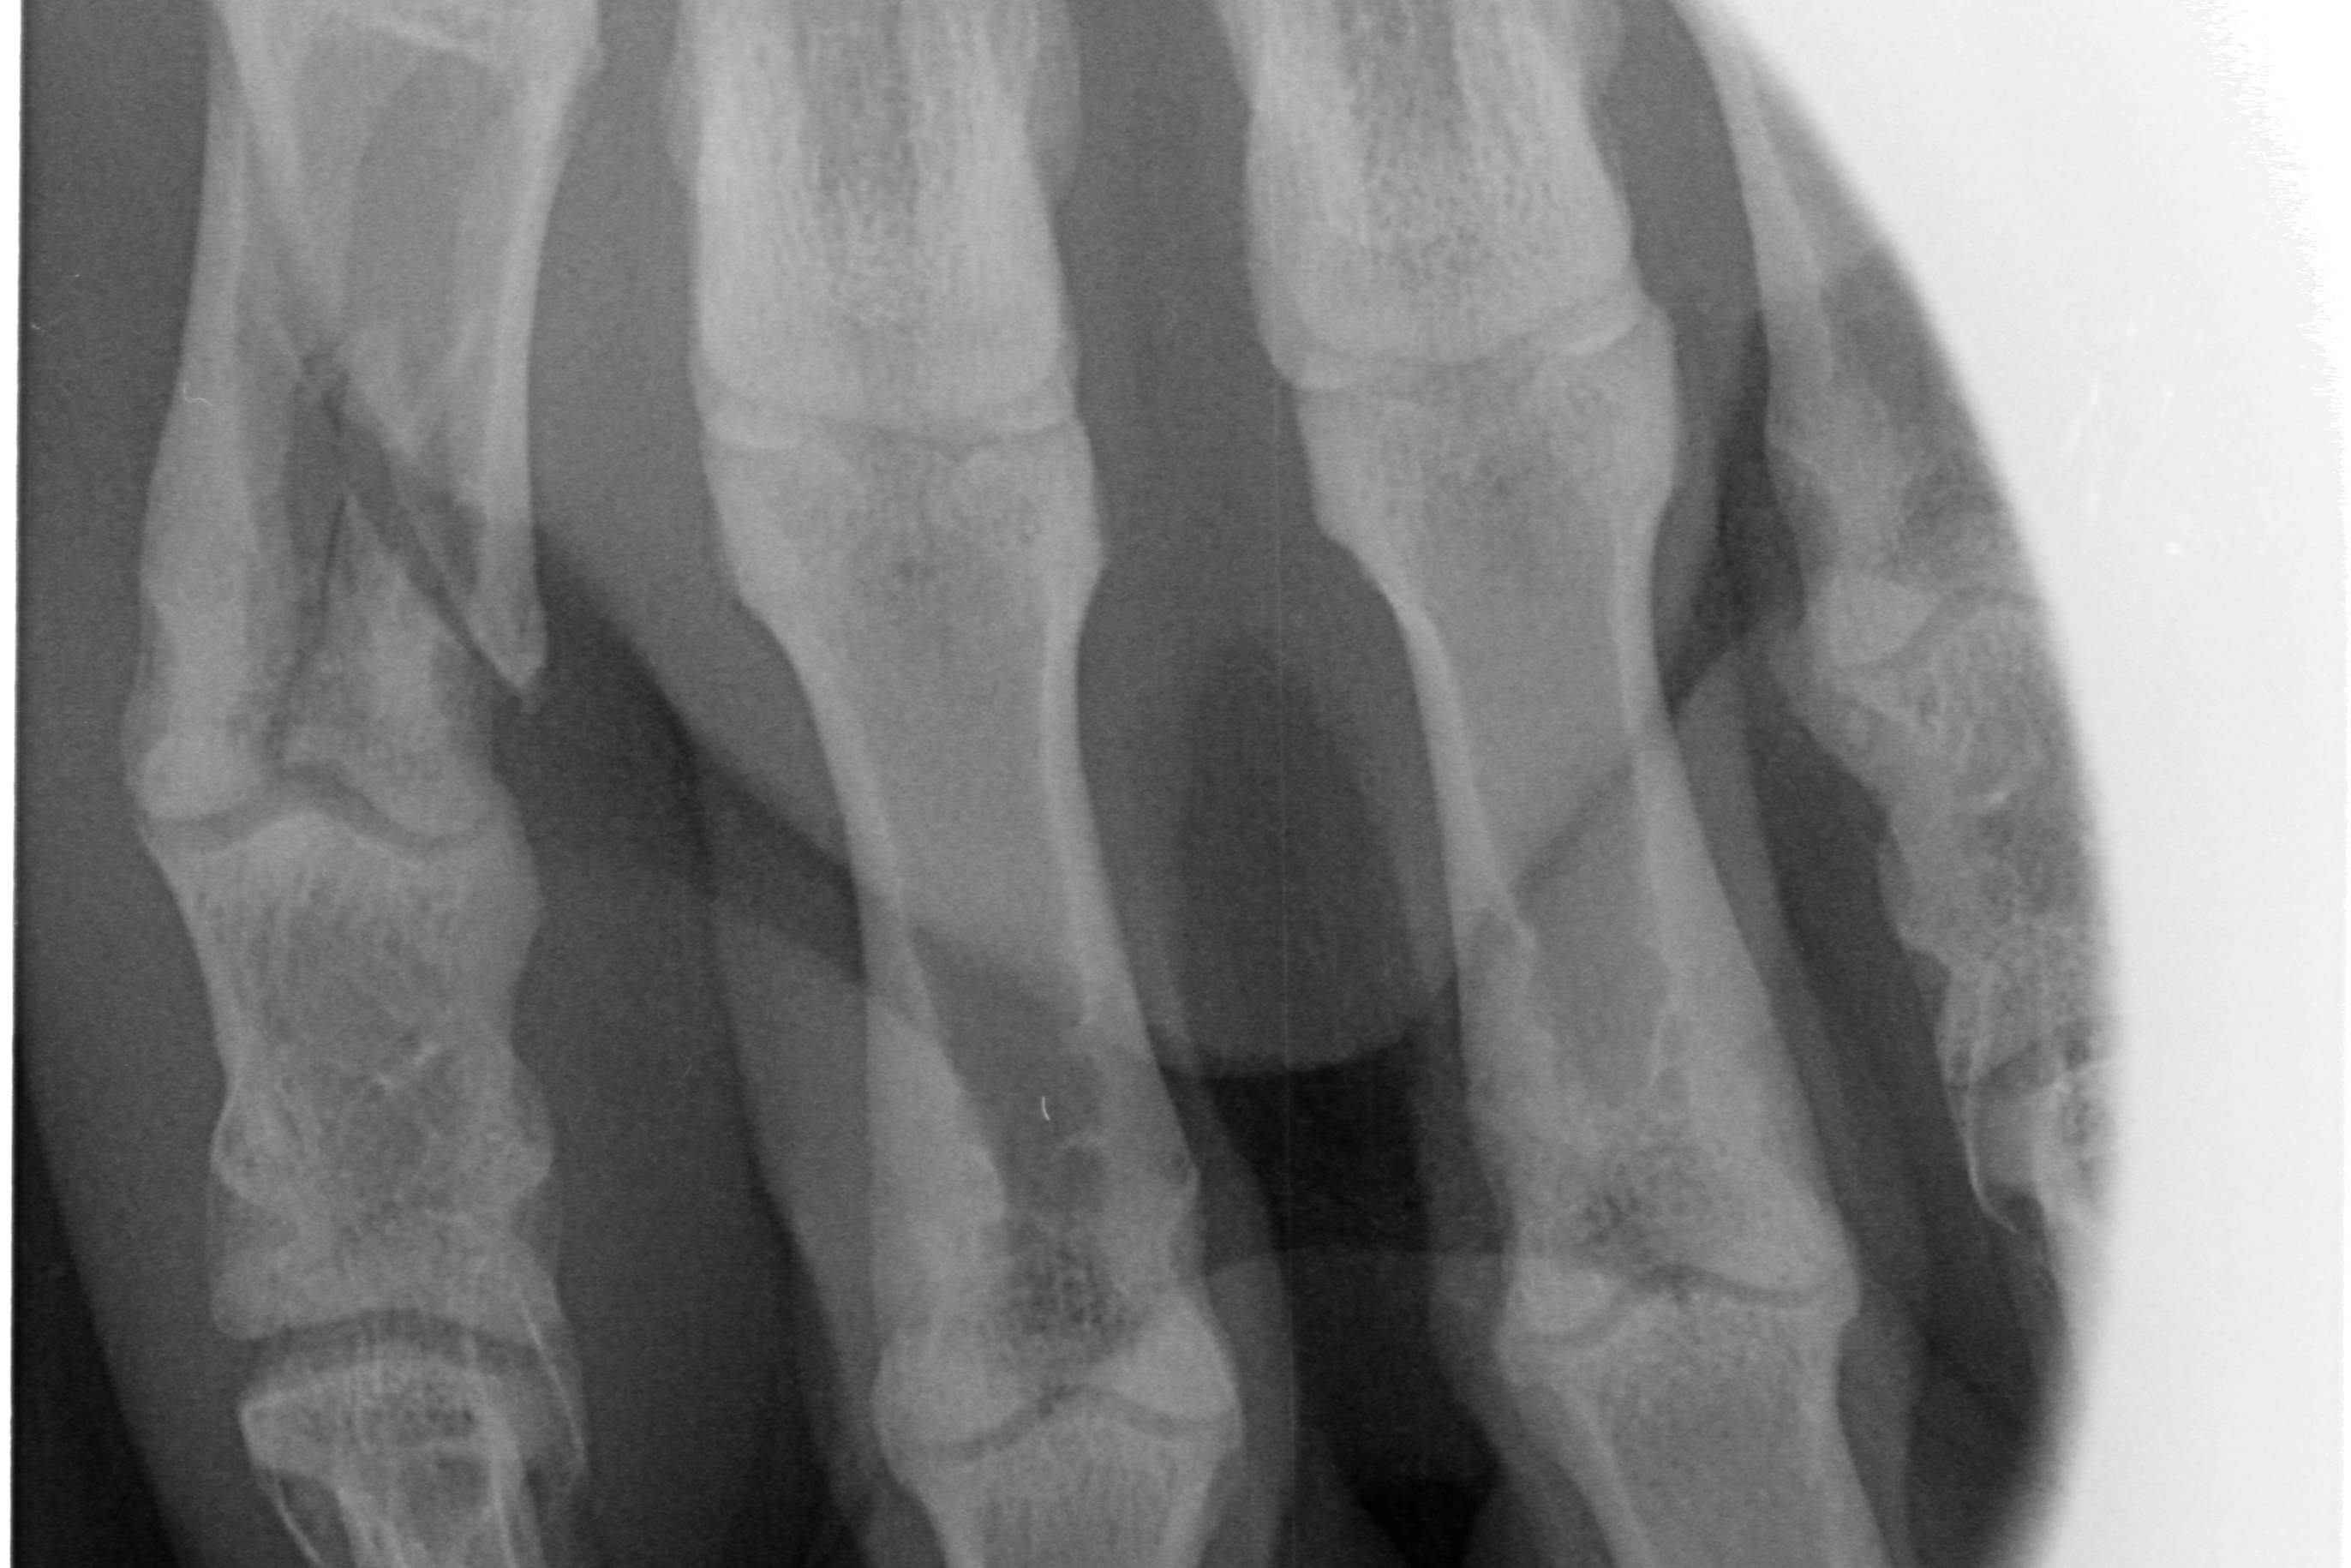

Auf diesen Bildern sehe ich etwas mehr als auf den herkömmlichen chemisch entwickelten Aufnahmen. Die Aufnahmen können vergrößert oder gefiltert werden. Sie lassen sich unkompliziert speichern und verschicken. Der Kunde kann eine Datei mitnehmen; der fachliche Austausch unter Tierärzten wird schneller.

Aber der Clou ist: Die Speicherfolien sind so klein, daß ich damit einen entscheidenden technologischen Vorteil gegenüber meiner alten Technik habe. Ich kann überlagerungsfrei jeden Zahn einzeln darstellen. Ich kann auch Pfötchen und Flügel röntgen, ohne gleich den ganz großen Apparatismus anzuwerfen.

Ein paar Beispielaufnahmen

aus unserer Röntgenpraxis